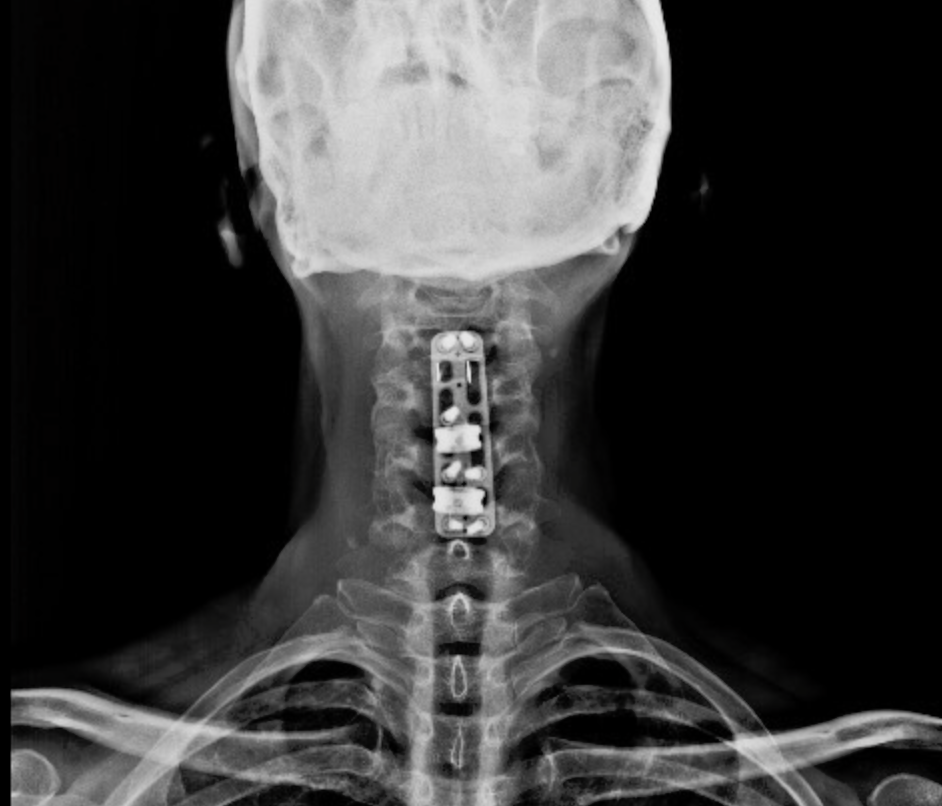

SURGERIES